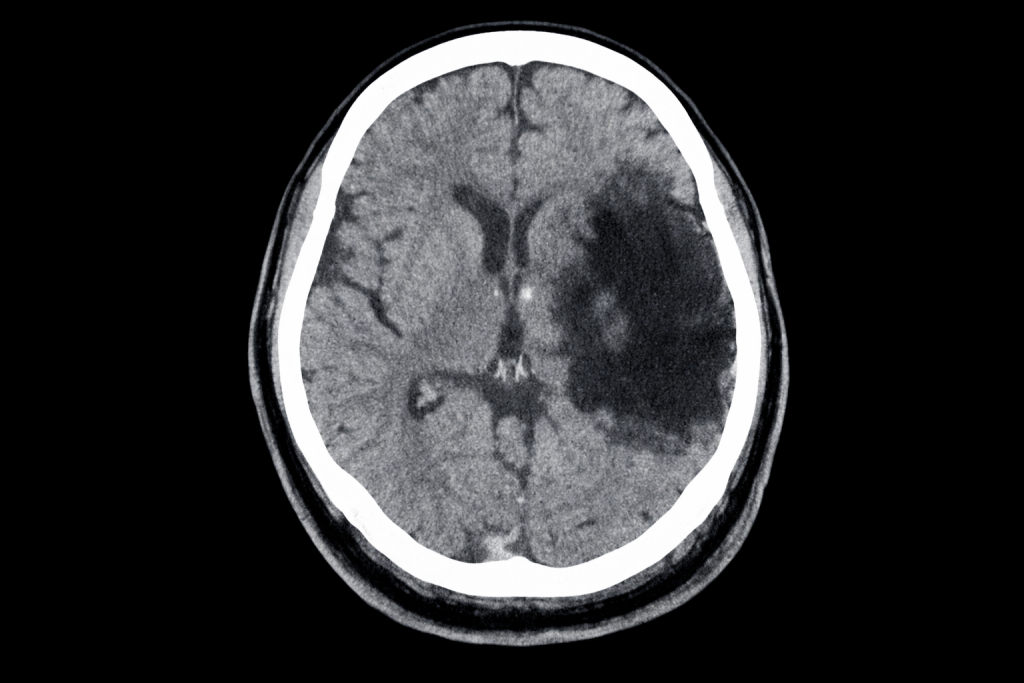

Por último, y lo más importante. Al no impulsar la sangre, en la aurícula izquierda pueden generarse trombos, sobre todo en personas con otras patologías que aumentan el riesgo de trombosis como hipertensión, diabetes, edad avanzada, ictus previo…

Estos coágulos pueden impulsarse a la circulación sistémica y provocar infartos cerebrales o en otros territorios. Se sabe que esta arritmia aumenta 5 veces el riesgo de sufrir un ictus. Esta es, por tanto, su principal complicación.